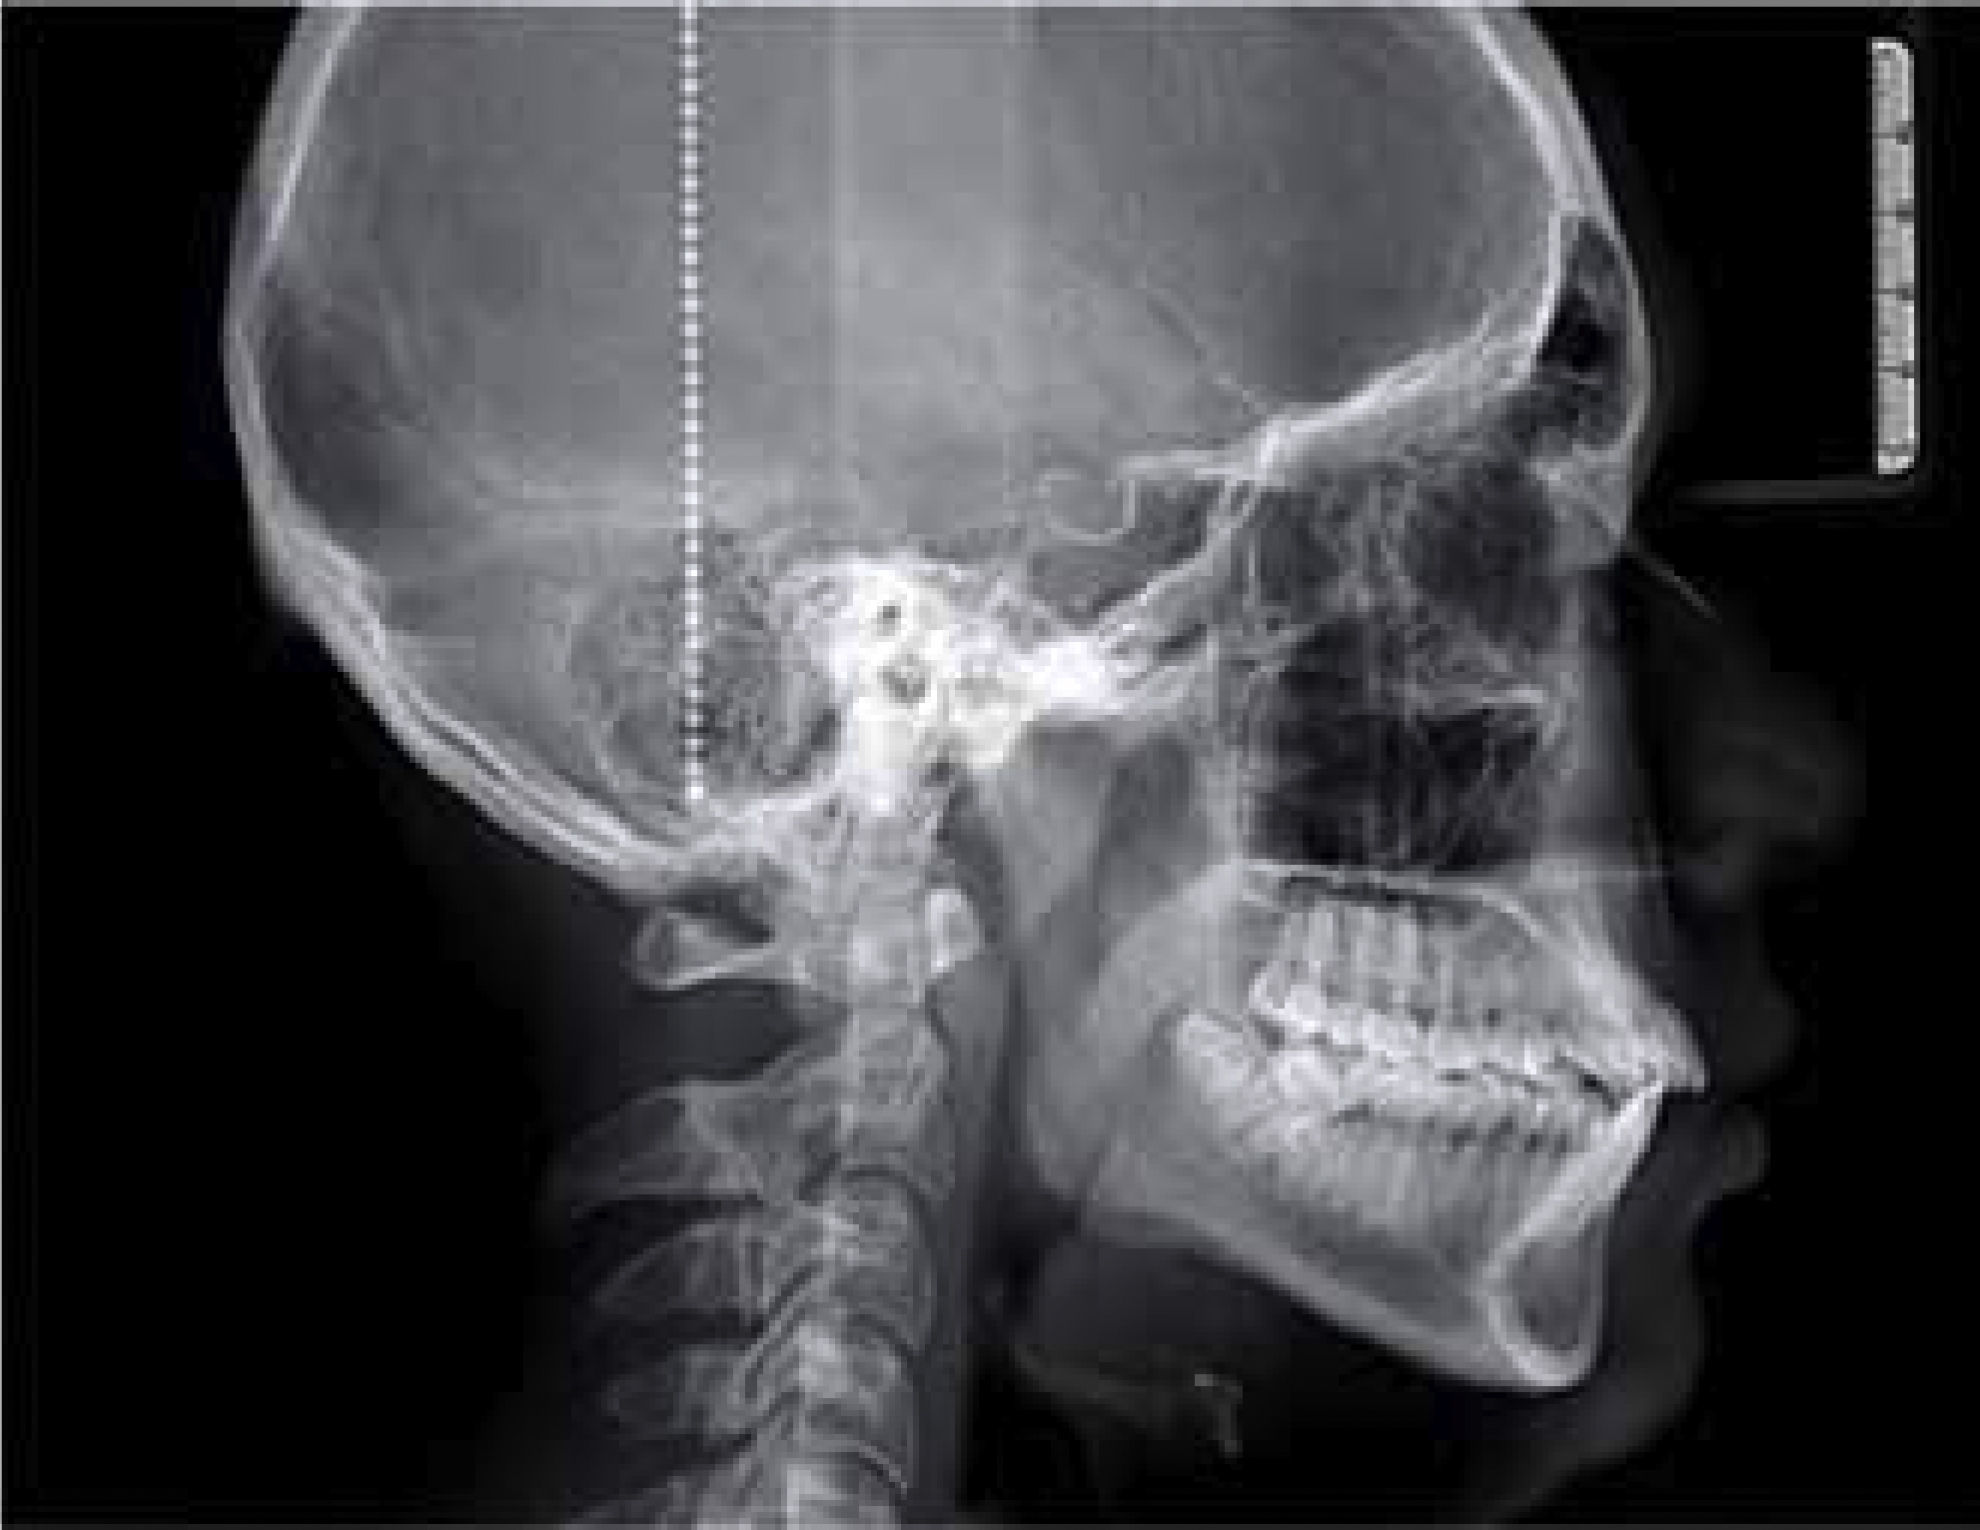

The cephalometric diagnosis was skeletal Class I patient with a brachifacial pattern and horizontal growth (CCW 71.6%) (Figure 4).